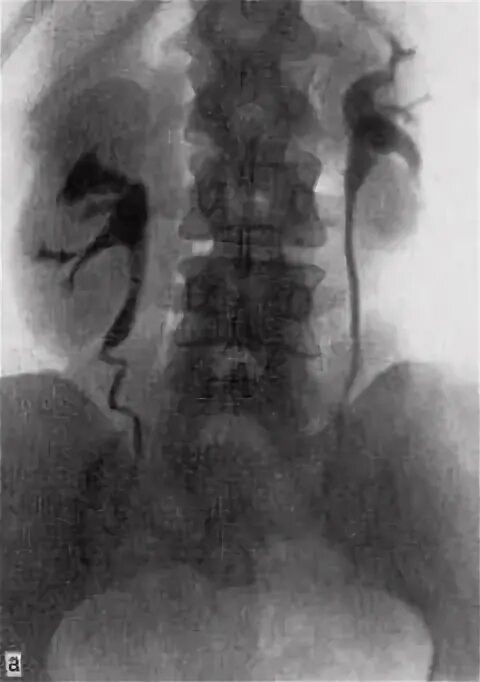

Опущение почки симптомы и последствия